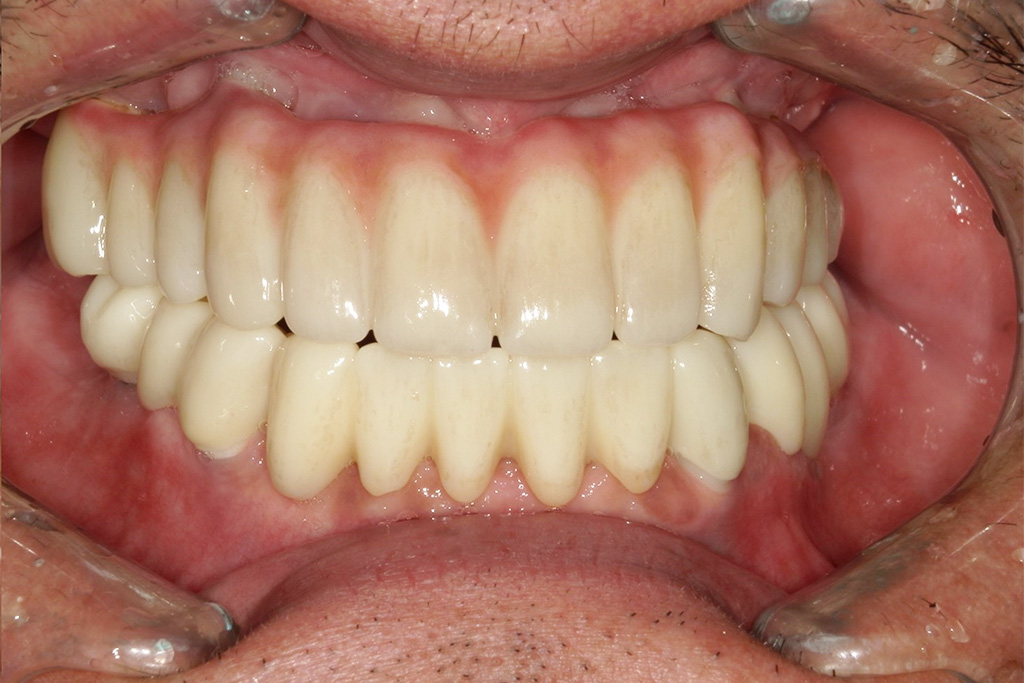

今回は噛めることと見た目の改善を目的として上顎はダメな部分は抜歯をし、インプラントを入れました。

現在では硬いものもかめてやってよかったと言われて私は満足しかありません。

| 治療の内容 | 上下オールオンXによるインプラント治療 |

| 必要な治療費 | 5,500,000円 |